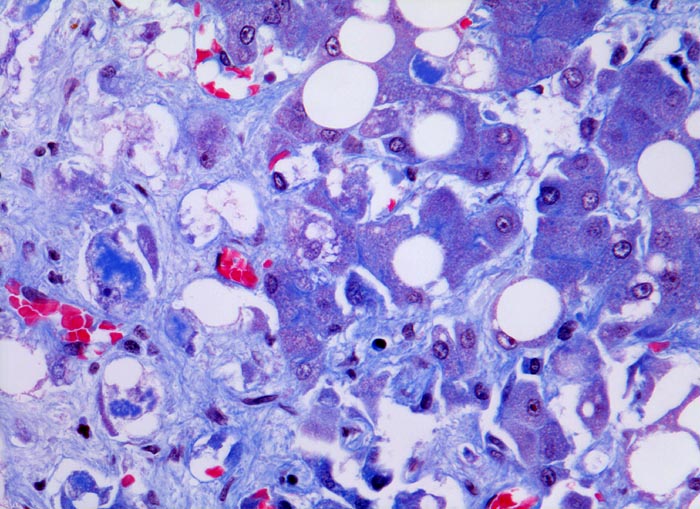

Meist findet sich eine grobtropfige oder gemischttropfige Verfettung des Parenchyms. Schon im Frühstadium der alkoholischen Steatohepatitis kann eine perizelluläre Maschendrahtfibrose, perisinusoidale und perivenuläre Fibrose mit Beginn in der Zone 3 festgestellt werden. Die Kombination von perivenulärer und perizellulärer (> 1096) Fibrose wird bei starker Ausprägung mit Arealen von dichter Kollagenfaserbildung auch als zentrale sklerosierende hyaline Nekrose bezeichnet. Wenn der Vernarbungsprozess fortschreitet, kann die perivenuläre Fibrosezone mit vernarbten Portalfeldern verschmelzen. Zentralvenen verschwinden oder sind stark in der Anzahl reduziert. Eine Phlebosklerose oder Obliteration der Zentralvenen kann hinzukommen. Breite Bänder von fibrotischem Gewebe mit Ductulusproliferationen und gemischtem Entzündungsinfiltrat umgeben die bei alkohlischer Zirrhose meist kleinen Regeneratknoten (=mikronoduläre Leberzirrhose mit Regeneratknoten von weniger als 3mm Durchmesser). Bei längeren Abstinenzphasen kann sich aufgrund der gesteigerten Regeneration auch eine gemischtknotige Zirrhose ausbilden. Ein gleichzeitiges Vorliegen einer Steatose oder Steatohepatitis (Steatose+neutrophile Granulozyten) in einer alkoholischen Leberzirrhose signalisiert in der Regel einen fortgesetzten Aethylabusus. Typisch für alkoholtoxische Leberschädigung sind Mallory-Denk Körperchen (> 3021), Megamitochondrien (> 3022) und eine Zellschwellung (=Ballonierung) aufgrund einer gestörten Albuminausschleusung. Oft können mässige Mengen von Hämosiderinablagerungen vor allem in den Kupffer Zellen nachgewiesen werden. Weitgehend identische morphologische Veränderungen wie bei der aethylischen Leberschädigung finden sich auch bei der nicht alkoholischen Steatohepatitis (NASH) d.h. bei Patienten, die keinen oder nur wenig Alkohol konsumieren.

Morphologische Merkmale:

• Zerstörte Läppchenarchitektur mit diffusem feinknotigem Umbau des Leberparenchyms.

• Breite Fibrosebänder mit Ductulusproliferation und gemischter Entzündung.

• Perivenuläre Fibrose und perizelluläre Maschendrahtfibrose in Zone 3.

• Verminderte Anzahl Zentralvenen.

• Mallory-Denk Körperchen

• Megamitochondrien.

• Hydropische Zellschwellung.

• Überwiegend makrovesikuläre, teils gemischttropfige Verfettung der Leberzellen.

• Intralobuläre Infiltrate neutrophiler Granulozyten (alkoholische Steatohepatitis: grobtropfige Verfettung, Maschendrahtfibrose und intralobuläre neutrophile Granuloyzten).